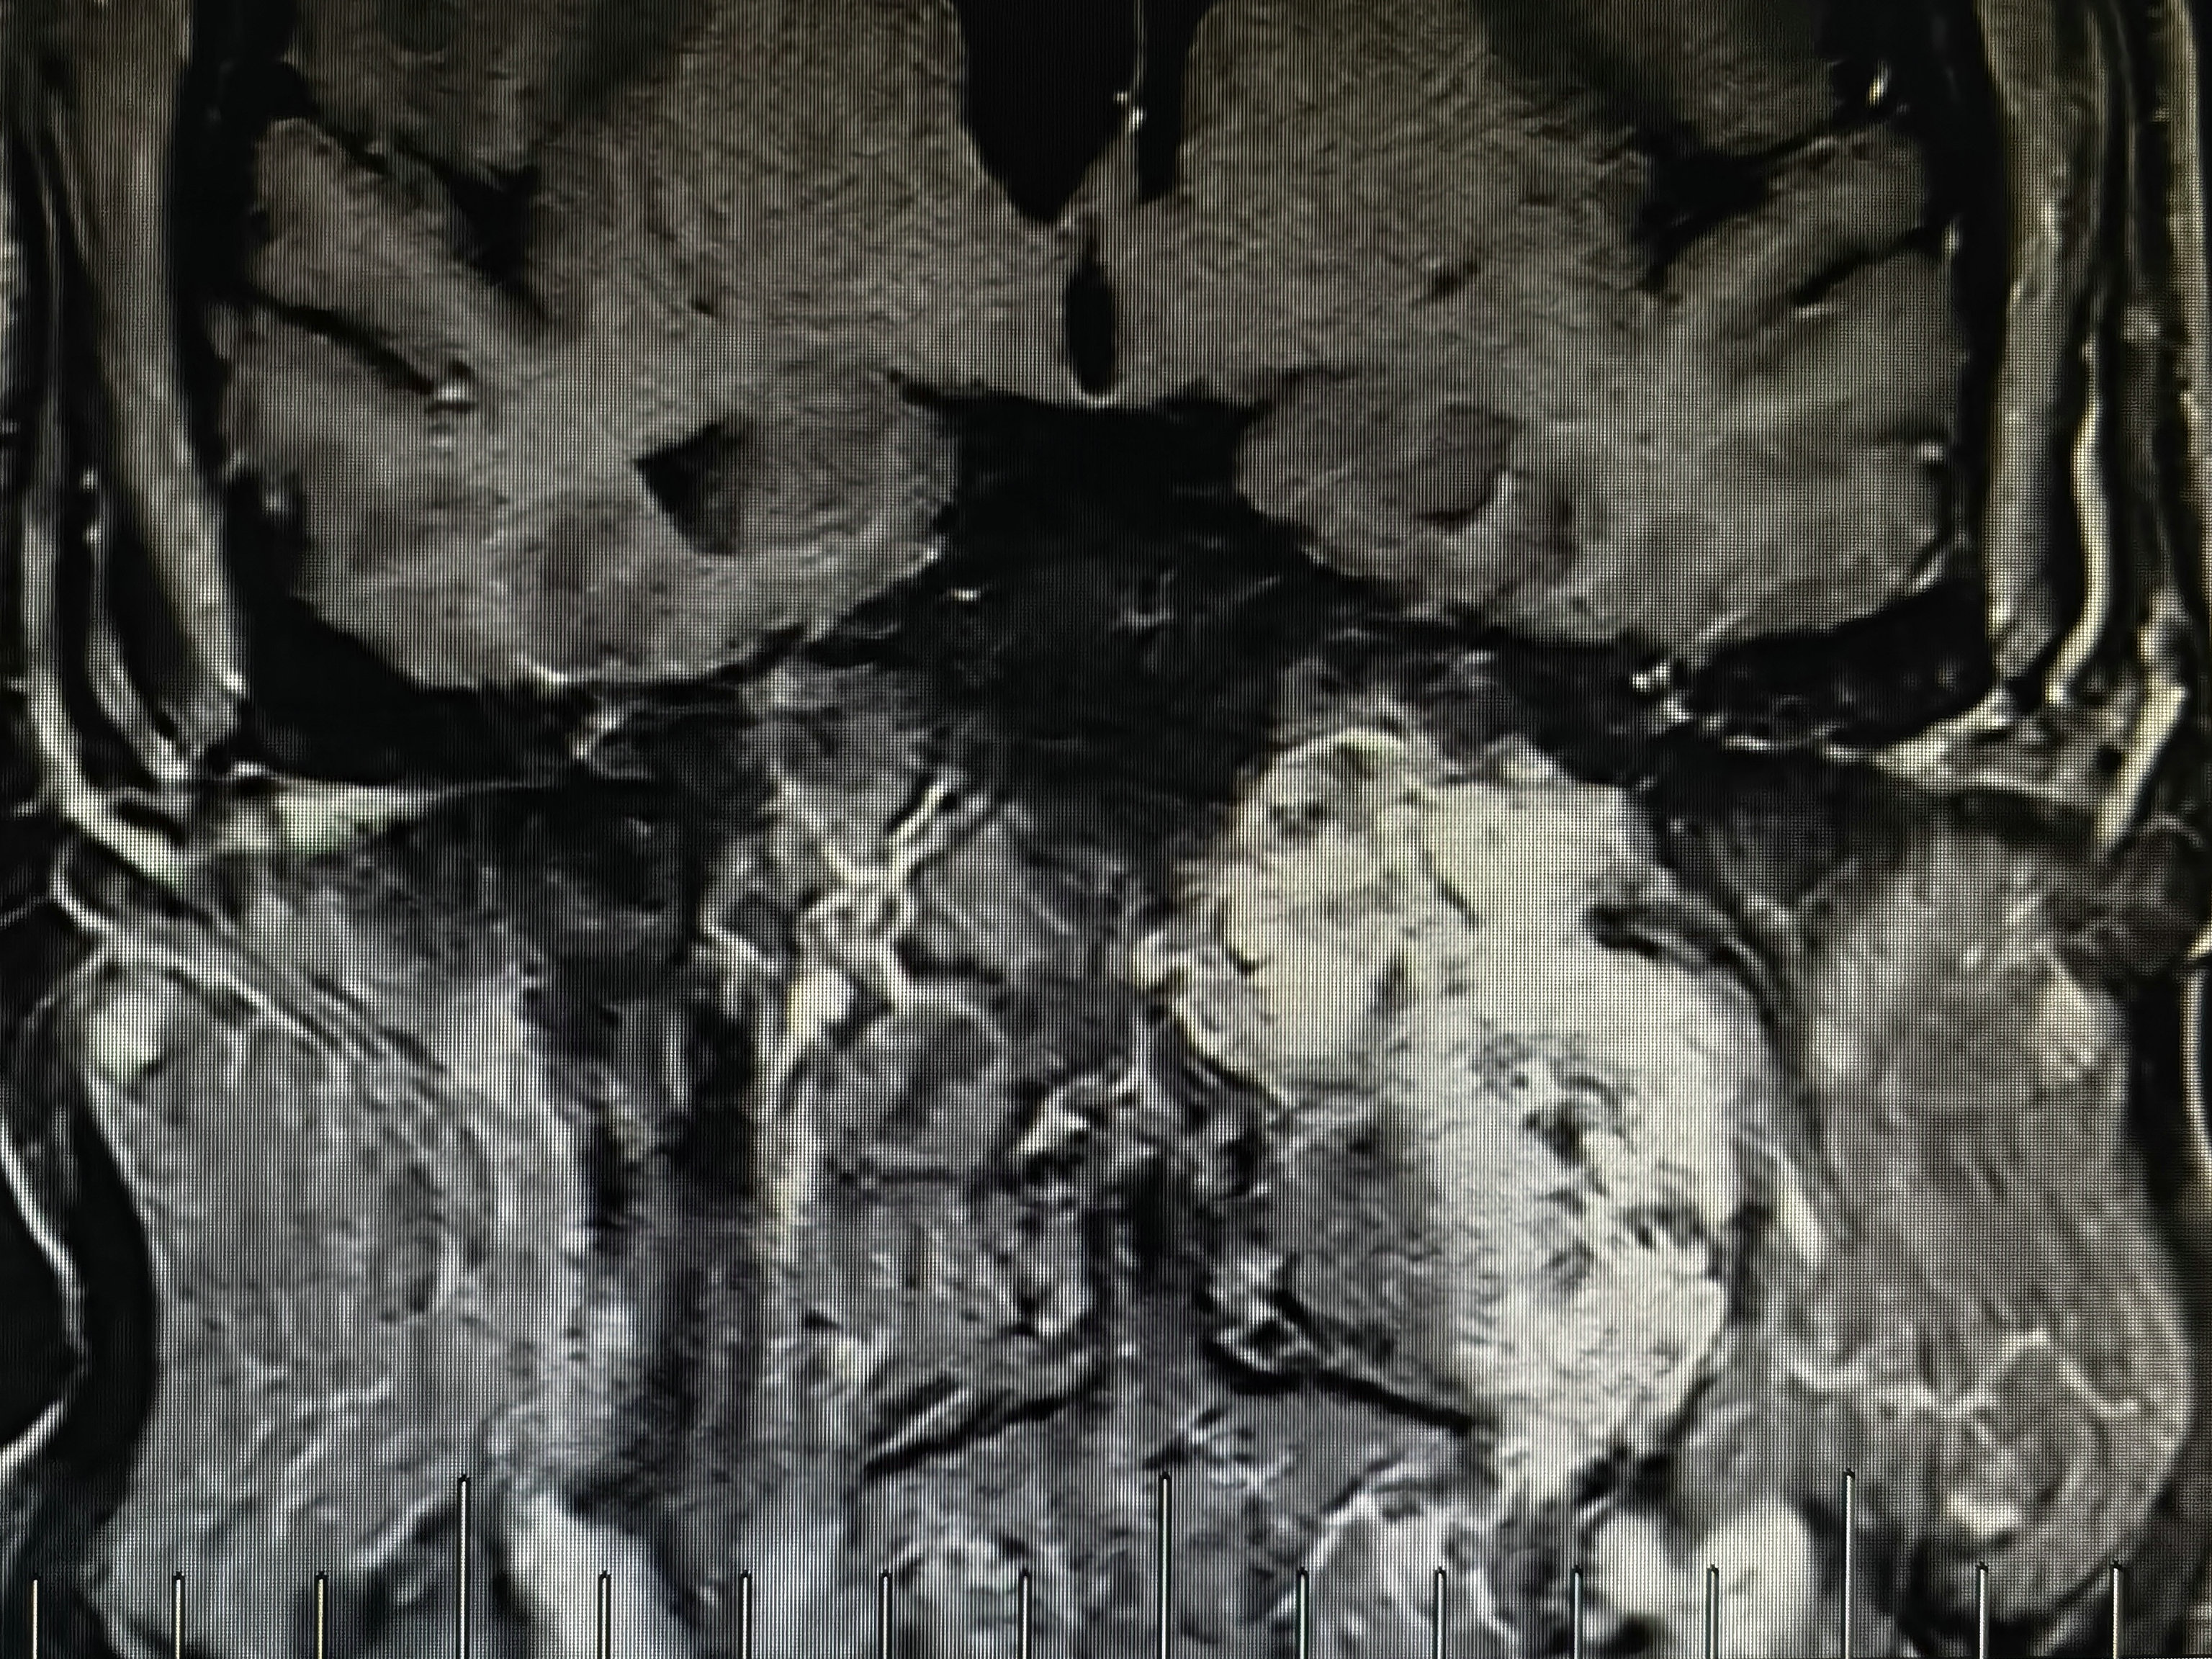

术前磁共振